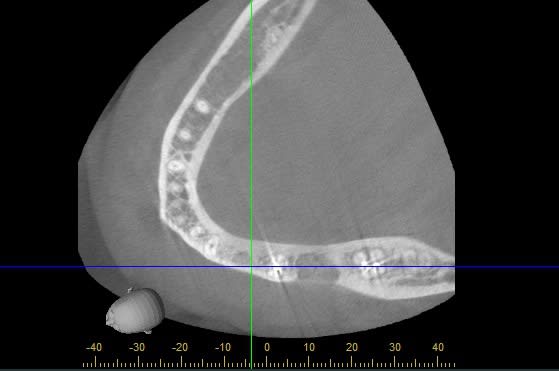

Faut il opter pour un implant de longueur 8x4.3 ou 10x4.3 (je pose du Nobel Replace CC), au vue des scanners ?

Je ne sais pas si un 8 mm suffit mais au vu du scanner (les implants dessinés font les vrais longueurs, cad 8.6 et 10.6mm.) je trouve que le trou mentonnier est proche...sachant que les forets sont encore plus longs que l'implant.

Je serais donc plus partante pour un 8mm, le 10mm me mettrait mal à l'aise dans ma faible expérience.

Scanner 34 avec un 8 mm hb4pob - Eugenol

Scanner 34 avec un 8 mm coupe ozt7vu - Eugenol

Scanner pour 34 avec un 10 mm x9x1yq - Eugenol